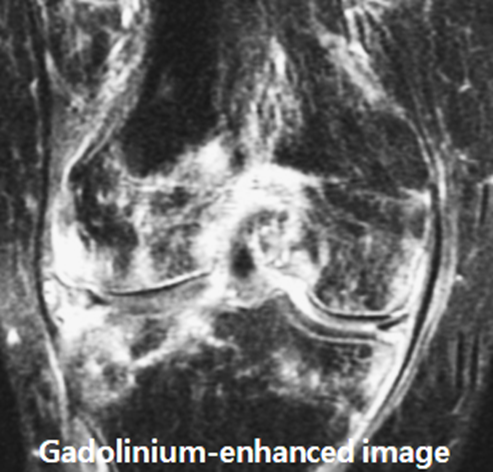

b. MRI

• High sensitivity for soft tissue and bone involvement

• T2-weighted images show:

• Subcutaneous hyperintensity (edema)

• Fascial thickening

• Rule out osteomyelitis or septic arthritis

MRI:

• Cellulitis: Demonstrates diffuse soft tissue edema and enhancement without bone marrow involvement.

• Osteomyelitis: Shows bone marrow edema, cortical destruction, and possible abscess formation.